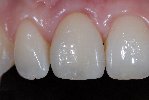

- Vollkeramische Restauration auf Implantat

- Vollkeramische Restauration auf vollkeramischen Abutment